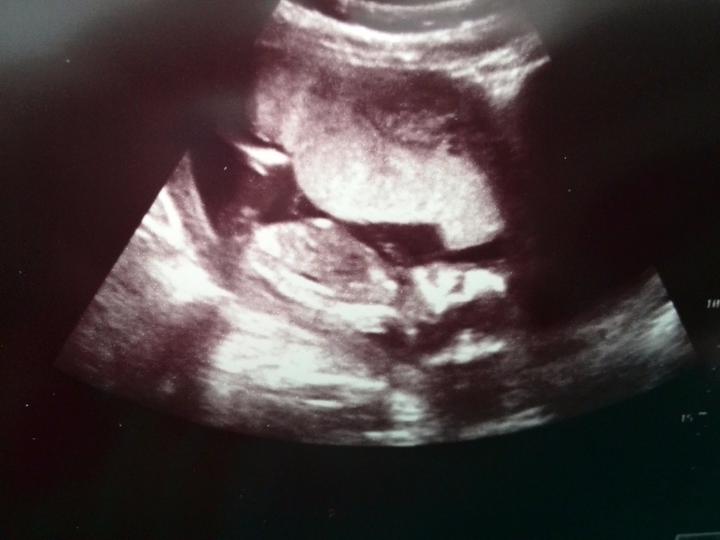

Zdravim, tak dnes kontrola u dr, Sebik je v pořádku akorad trošku cvalik 😀 ve 32tt vazime 2100g takze zadnej drobecek 🙂 a kolik vazi Vase stesticka?

Zdravím Vás dámy 🙂 tak dnes kontrola 20+1tt a už nám potvrdili že budeme 100% chlapák 🙂 fotečku bohužel nemám, mám video ale to netušim jak se sem dává 🙂 vše je v pořádku a rosteme jako z vody... délka od hlavičky k zadečku 15cm a váha 400g... už ted se těšim až náš poklad zase uvidim 🙂